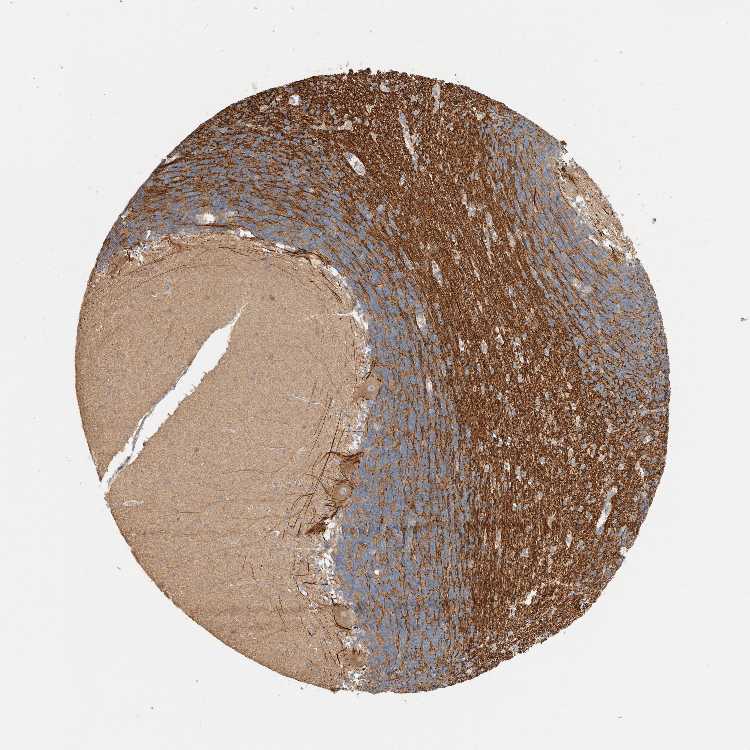

BRAIN CEREBELLUM Show tissue menu

CEREBELLUM - Expression summary

CEREBELLUM - Antibody stainingi

Antibody staining in the annotated cell types in the current human tissue is reported as not detected, low, medium, or high, based on conventional immunohistochemistry profiling in selected tissues. This score is based on the combination of the staining intensity and fraction of stained cells.

Each image is clickable and will lead to virtual microscopy that enables deeper exploration of all samples and also displays staining intensity scores, fraction scores and subcellular localization as well as patient and tissue information for each sample.

Antibody HPA023585Antibody HPA024547

Purkinje cells MediumMedium

Cells in granular layer LowMedium

Cells in molecular layer Not detectedNot detected